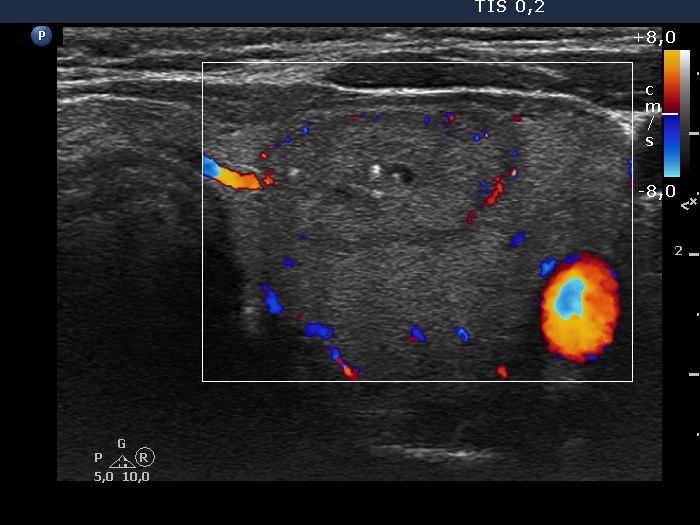

Intranodular hyperechogenic figures - case 1518 (ultrasonographic picture 7)

Left lobe, horizontal scan, color Doppler mode.. The nodule has perinodular blood flow.